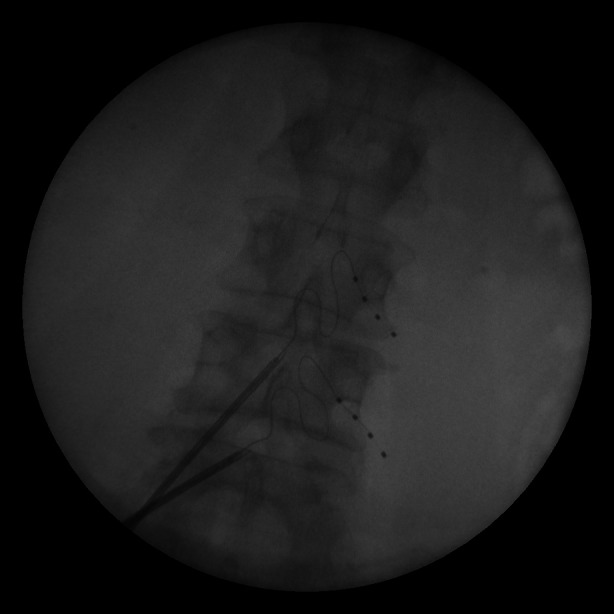

Abstract Image